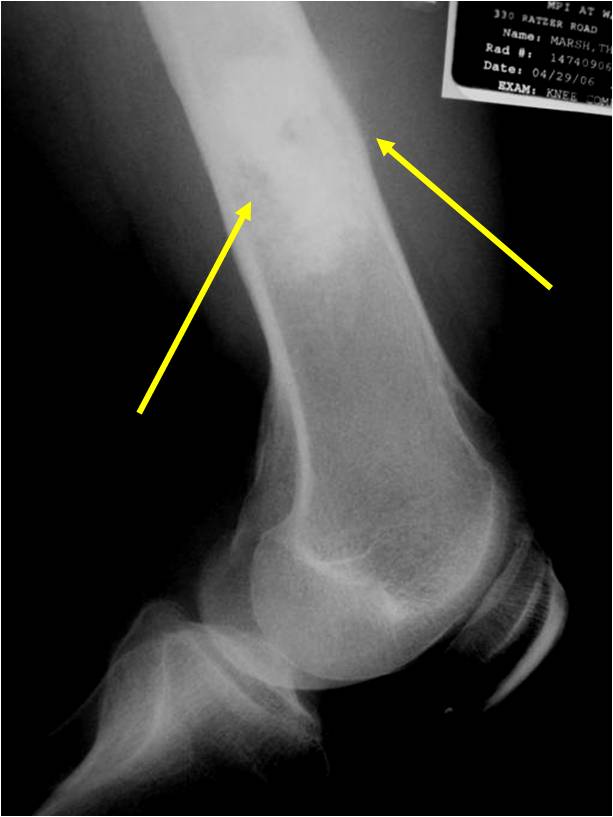

Radiology emulates pathology: Biphasic Tumor

- One region low grade chondrosarcoma

- Second more aggressive area with bone destruction, lysis of calcification, soft tissue mass

- Cortical permeation and a soft tissue mass in 70% of cases

Ill-defined, lytic intraosseous lesion

Characteristically abrupt transition between chondroid tumor and dedifferentiated, lytic component

Bone may be expanded and adjacent cortex thickened

(Right Arrow)Aggressive Lytic Area (Dedifferentiated Sarcomatous Component) Cortical Destruction Soft Tissue Mass without Calcification